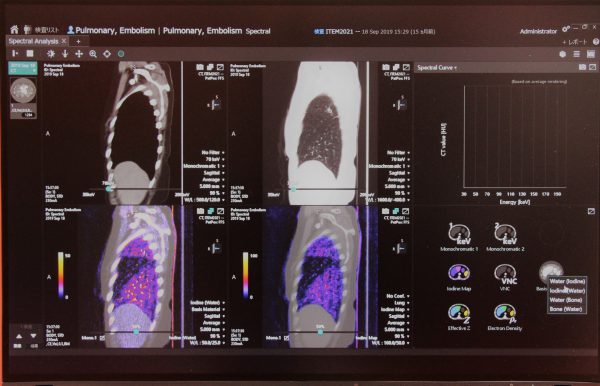

AIと医療スタッフが協調して画像診断をサポートする、読影診断支援ソリューション(Abierto / Reading Support Solution)。

脳血管疾患患者のQOLを高めるためSTROKEは、脳卒中疾患へのワークフロー改善を目的としたDeep Learning技術を内蔵した画像アプリケーションを搭載し、読影までのプロセスを自動化して速やかに検知情報を提供することで、治療方針策定を支援。また、新しい医療情報ソリューション「Abierto」シリーズでは、患者の治療や検査の情報を時間軸で統合し、医師別や診療シーン別に最適の情報を提供する。3D医用画像解析システムAZE Virtual Placeは、各種画像診断用途に対応した数多くの解析機能を備える。